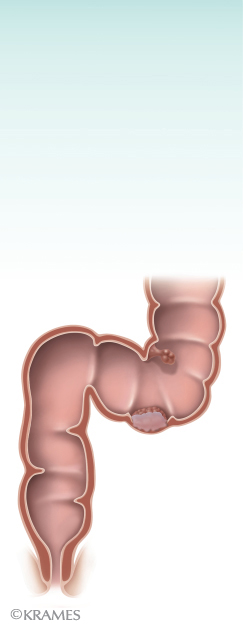

La colonoscopía es un examen para visualizar el colon o intestino grueso. El colon mide alrededor de (6) pies en la mayoría de los adultos.

- Se insertará un colonoscopio a través del recto hacia el colon. El colonoscopio es fino y flexible y contiene una luz y una lente.

- El médico va a dirigir el colonoscopio a través del colon hacia la unión del intestino grueso con el delgado.

- El objetivo principal de la colonoscopía es la detección de pólipos, salvo que le indiquen el examen debido a otras razones.

- La colonoscopia puede utilizarse para examinar y detectar cáncer o pólipos precancerosos. También se utiliza para examinar el intestino grueso a fin de detectar otras enfermedades diferentes.